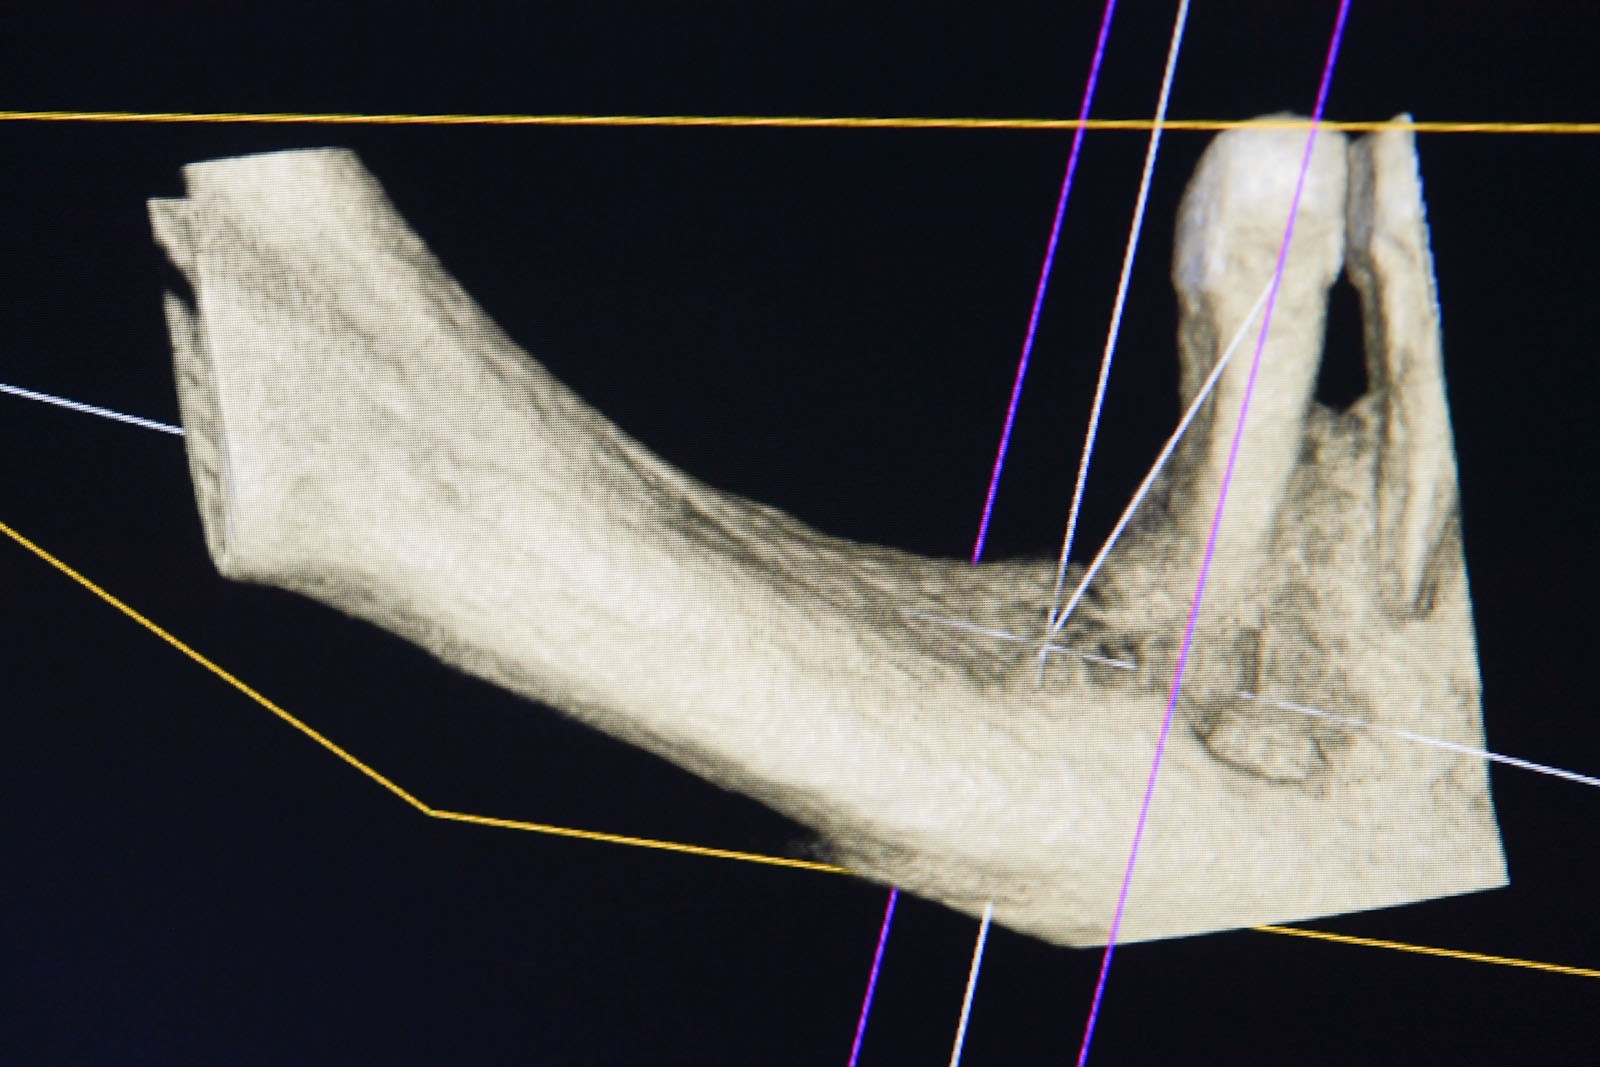

Przed podjęciem leczenia należy określić stopień zaniku kości szczęk oraz żuchwy. W tym celu przeprowadza się badanie kliniczne oraz odpowiednią diagnostykę obrazową pacjenta. Uwzględnia ona zdjęcie panoramiczne OPG jako podstawę dwuwymiarowego obrazowania podłoża kostnego oraz możliwe jest badanie tomograficzne CT lub bardziej precyzyjna tomografia stożkowa CBCT. Opcjonalnie wykorzystywana diagnostycznie tomografia pozwala na bardziej wnikliwą ocenę stopnia zaniku kości w trójwymiarowym, przestrzennym obrazie.

Precyzja projektu druku siatki bazuje na dokładności odwzorowania kształtu kości w stożkowej tomografii komputerowej CBCT, co zapewnia ich dobre przyleganie do podłoża kostnego oraz ogranicza powstawanie powikłań w postaci obnażania się siatek.